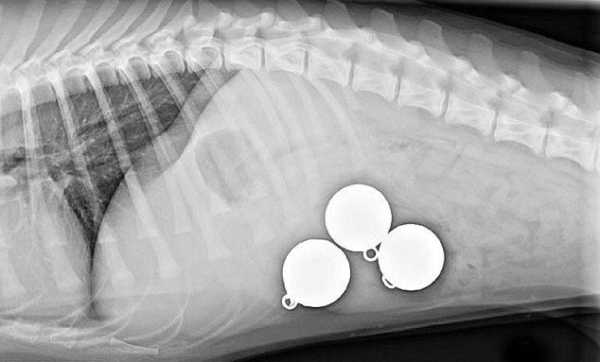

Лабрадор, що проковтнув 3 масивних рибальських грузила

Три 200-грамові грузила витягнуті з його шлунка